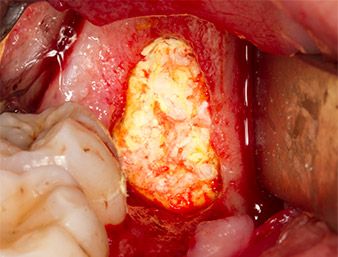

Subsequently, the autogenous bone tissue (Fig. 13) was placed into the alveole and the surrounding bone defect (Fig. 14). Collagen fleece covered the bone chips up to bone level as protection for the exposed nerve (Fig. 15). Sutures using vicryl thread, USP 4.0, were used to close the opened up soft tissue (Fig. 16). An Ibuprofen preparation (Seractil 400 mg, 3x1) and an antibiotic consisting of amoxicillin and clavulanic acid (Augmentin 1 g, 2x1) were prescribed postoperatively.

In autogenous bone chips, harvested using a piezo surgical technique in the case study, bone cells appear to have a better chance of survival than when using rotary preparation (16). This is an advantage for wound healing. As is usual at the University Dental Clinic Vienna, to optimize hygiene and consequently the healing process, suction with bone filter was not used during the preparation.